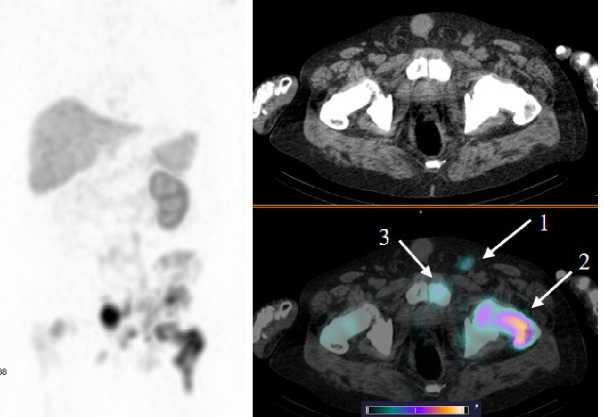

Рис. 5. MIP-реконструкция, КТ и совмещенное ОФЭКТ/КТ изображение больного раком предстательной железы с множественными метастазами в кости и лимфатические узлы малого таза через 2 ч после инъекции [99mTc]Tc-HYNIC-PSMA. На ОФЭКТ-КТ изображении стрелкой отмечено накопление РФЛП в паховом лимфатическом узле слева (1) SUVmax 22; бедренной кости слева (2) SUVmax 53; лонной кости слева (3) SUVmax 22,8

Fig. 5. MIP reconstruction, CT and SPECT/CT image of a patient with prostate cancer with multiple metastases to bones and pelvic lymph nodes 2 hours after injection of [99mTc]Tc-HYNIC-PSMA. Аccumulation of radiopharmaceutical in the pathological areas is indicated by the arrow on the SPECT-CT image: inguinal lymph node on the left (1) SUVmax 22; femur on the left (2) SUVmax 53; pubic bone on the left (3) SUVmax 22.8